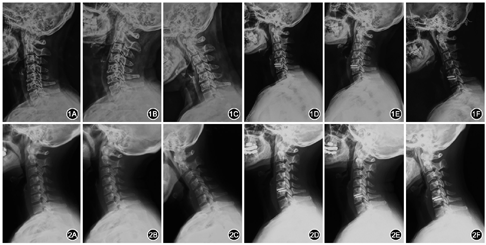

ACDR手术节段HO低分级组典型病例见图1,患者女,40岁,因颈椎病接受C5/6节段ACDR手术。ACDR手术节段HO高分级组典型病例见图2,患者女,43岁,因颈椎病接受C5/6节段ACDR手术。